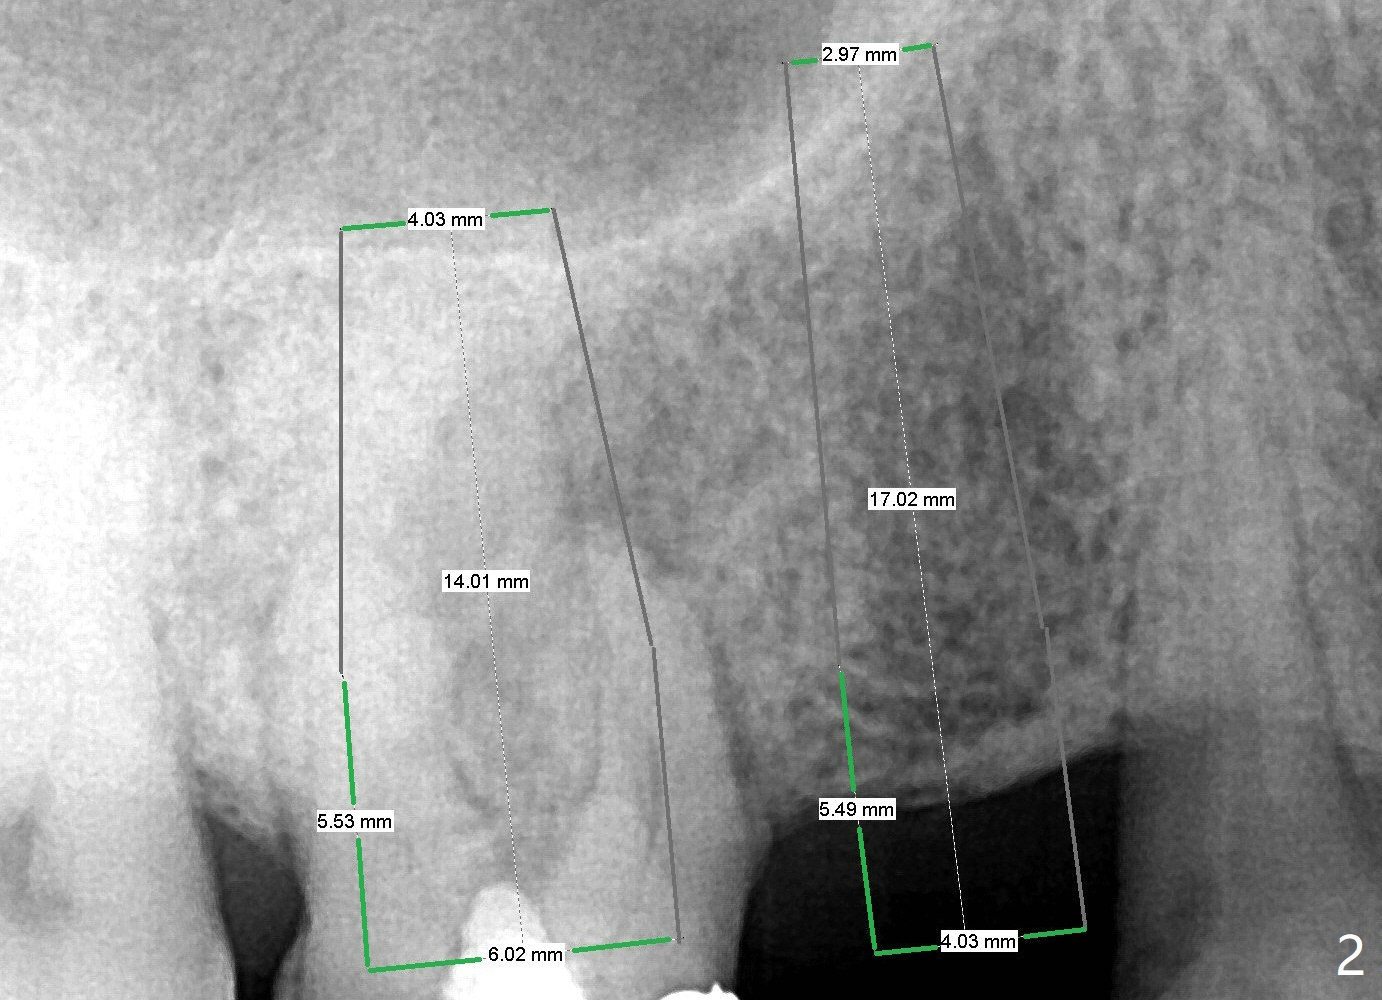

A 67-year-old man used to have a 3/4 cantilever bridge, which is dislodged (Fig.1). The anchor tooth has a buccal fistula with apparent furca perforation and mesiobuccal periapical radiolucency (<). Prior to extraction, the tooth will be used as a surgical guide for implant placement at #4 (Fig.2). Since the bone density at #4 seems to be low (*), bone expander kit will be used.